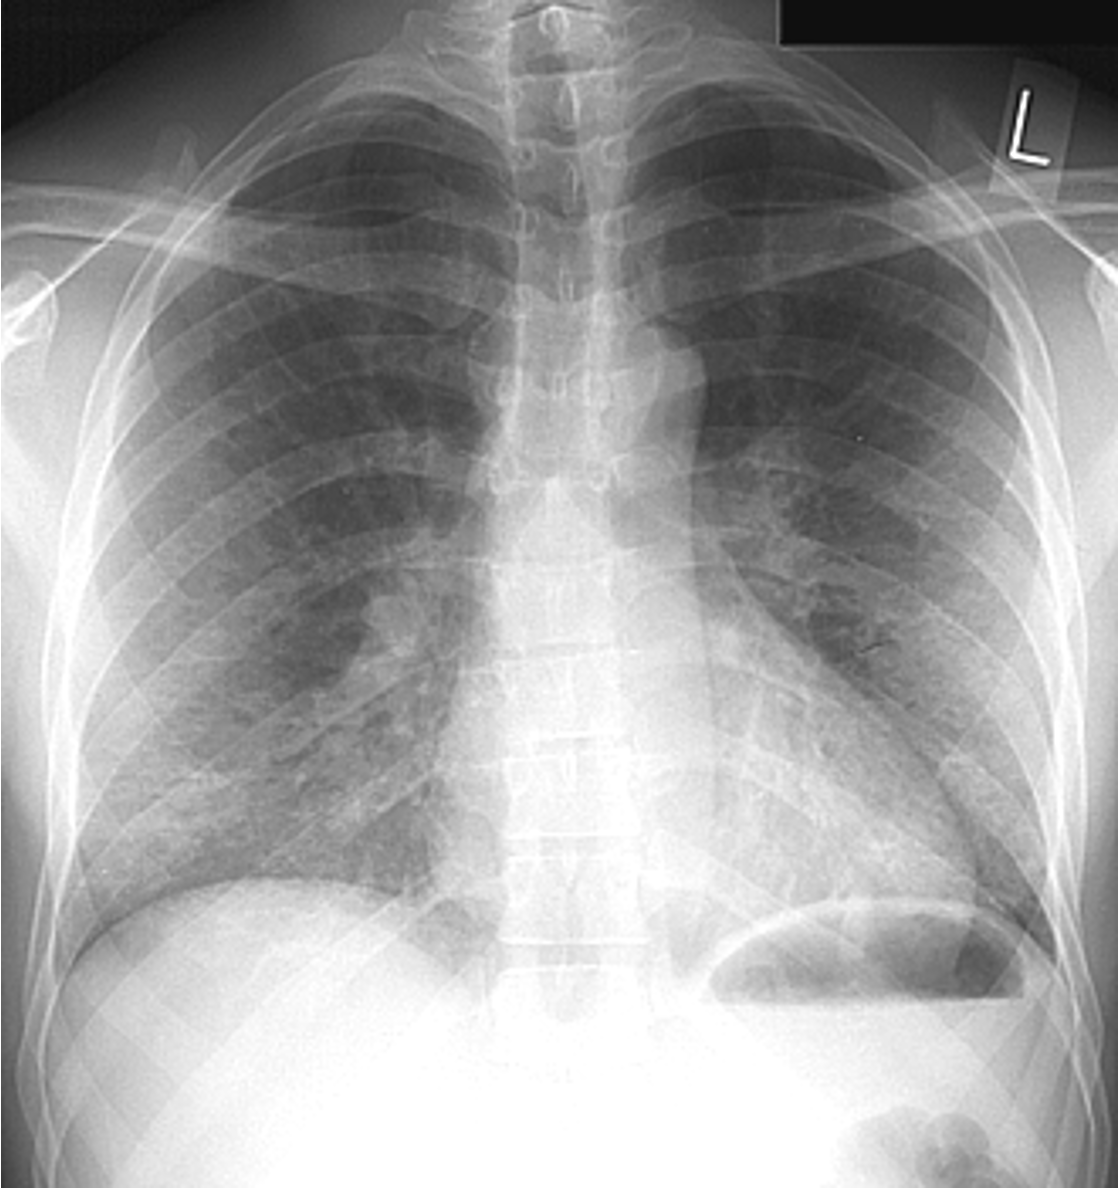

Air space pathology infiltrates: ______ & ______

alveolar & interstitial

Which type of infiltrate tends to be localized

alveolar

Which type of infiltrate is diffuse?

interstitial